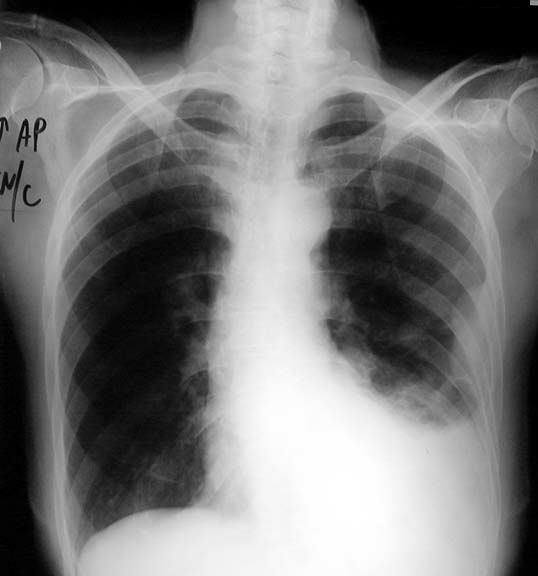

Other finding include:

Chest wall mass

• Extrapleural sign

• Ribs intact

• Parietal pleural mass

• Lateral decubitus showing shift of fluid, with persistent mass at its location